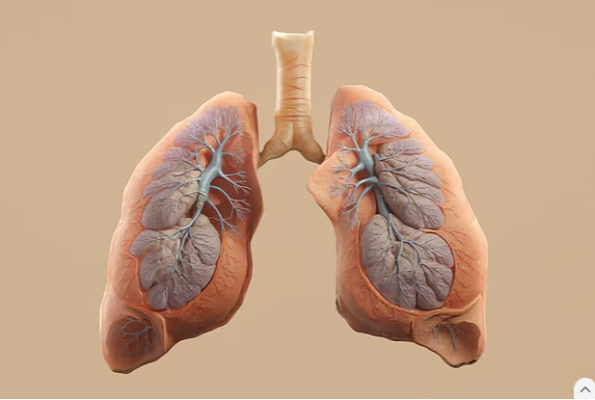

অনেকেই ভাবেন, সিগারেটের চেয়ে ই-সিগারেট বা ভেপ অনেকটাই নিরাপদ। কিন্তু গবেষণা জানাচ্ছে, ই-সিগারেট থেকেই হতে পারে ফুসফুস এবং মুখের ক্যানসার। দেরি হয়ে যাওয়ার আগেই এ বিষয়ে সচেতনতা গড়ে তোলার পরামর্শ দিয়েছেন গবেষকেরা। গত মার্চ মাসে ‘কারসিনোজেনেসিস’ জার্নালে প্রকাশিত হয়েছে এই গবেষণাপত্র। এ কাজে নেতৃত্ব দিয়েছেন সিডনির ইউনিভার্সিটি অব নিউ সাউথ ওয়েলসের ক্যানসার গবেষকেরা। ২০১৭-২০২৫ সালের মধ্যে প্রকাশিত রোগীদের উপাত্ত (কেস রিপোর্ট), প্রাণীদের ওপর করা গবেষণা (অ্যানিমাল স্টাডি) এবং ল্যাবরেটরির গবেষণার বিস্তারিত বিশ্লেষণ করেছে এই দলটি।

এই গবেষণায় ই-সিগারেটের সঙ্গে দেহের এমন পরিবর্তনের সরাসরি সংযোগ পাওয়া গেছে। তিনি বলেন, এতে কোনো সন্দেহ নেই যে ই-সিগারেটের ধোঁয়ায় মুখ, মুখগহ্বর এবং ফুসফুসের কোষে অস্বাভাবিক পরিবর্তন আসে।

তবে বার্নার্ড স্টুয়ার্ট যে শারীরিক পরিবর্তনের কথা জানিয়েছেন, তা ক্যানসারেরই ইঙ্গিত দেয়। দন্তচিকিৎসকেরা মুখের ক্যানসারে আক্রান্ত এমন ব্যক্তিদের বিষয়ে জানিয়েছেন, যাঁরা কখনো সিগারেটে টান না দিলেও ই-সিগারেট সেবন করেছেন।

গবেষণাটির প্রধান, রোগতত্ত্ববিদ, সহযোগী অধ্যাপক ফ্রেডি সিটাস জানান, সিগারেট যে ফুসফুস ক্যানসারের কারণ, তা নিশ্চিত করতে এক শ বছর লেগেছিল।